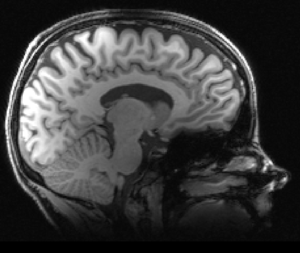

I went to secondary school in the Netherlands to the Stedelijk Gymnasium Nijmegen. I then did an undergraduate degree in Liberal Arts & Science at University College Utrecht, majoring in psychology, economics and mathematics. After this, I did a 2-year research master’s degree at Maastricht University in Neuroeconomics, a mixture between neuroscience and economics. I am currently enrolled in the Wellcome Trust Doctoral Training Programme in Neuroscience at the University of Oxford.